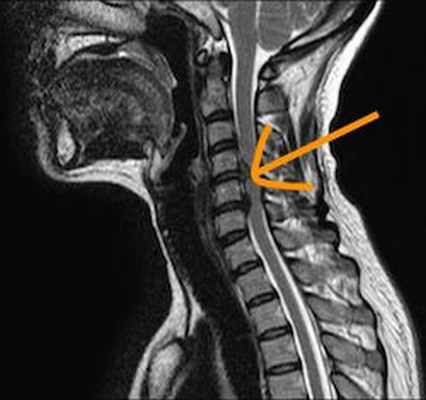

Для точной диагностики грыжи шеи пациенту необходимо сделать МРТ шейного отдела позвоночника и с его результатами прийти на консультацию к неврологу или вертебрологу. Выглядеть на МРТ грыжа шейного отдела позвоночника будет как заметное выбухание в области межпозвоночных дисков.

Как выглядит грыжа на МРТ

| МРТ снимок - грыжа поясничного отдела позвоночника | МРТ снимок - грыжа шейного отдела позвоночника | МРТ снимок - грыжа грудного отдела позвоночника |

![]() | ![]() | ![]() |